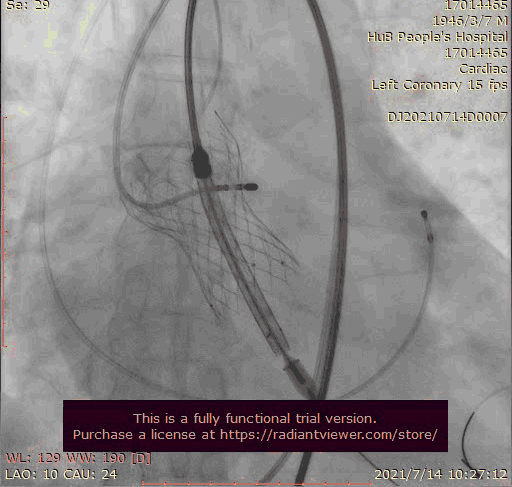

大结构瓣膜稳定性差,输送器使瓣膜跳到瓣上

奇思妙想使用射频消融大头压住支架至窦底

在大头压迫支架下释放第二个瓣膜

第二个支架完美释放固定第一个支架

术后基本无返流

1.在第一次释放瓣膜时,由于患者主动脉根部瓣上瓣下均比瓣环平面大,受到血流的冲击,瓣膜滑至较深的位置,使用venus-A PLUS回收

2.回收后重新定位释放,由于第一次滑至较深,第二次稍微卸力后瓣膜跳至窦上,使用venus-A PLUS回收,再次重新定位

3.第三次释放瓣膜后位置的把控非常精准,瓣膜位置合适,但由于稳定性差,撤出输送系统时瓣膜跳至窦上,此时非常凶险,瓣膜无法固定住,受到血流的冲击,可能对升主造成夹层的风险,一般会选择开胸取出,但风险非常,在江洪教授的思考下和团队的讨论下,决定使用射频消融大头穿过支架网孔使瓣膜到窦底固定,在此基础上释放第二个瓣膜,使用第二个瓣膜花冠固定住第一个瓣膜

4.第四次瓣膜释放后两个瓣膜均稳定住,造影超声评估无瓣周漏,二尖瓣反流也基本消失,观察一小时后,无其他情况。患者顺利下台